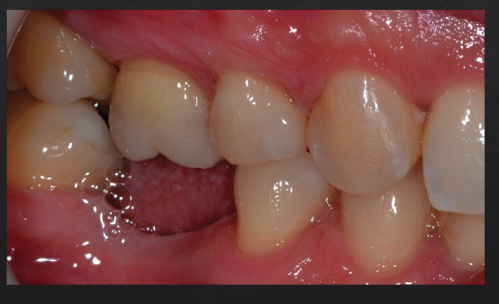

Posterior bite collapse as a result of 1st molar extraction demonstrates multiple occlusal issues that may result in periodontal problems such as

Super-eruption, resulting in root and furcation exposure

Molar tipping, creating a pseudopocket (5)

Open contact, a risk factor for food impaction and gingival inflammation (4)